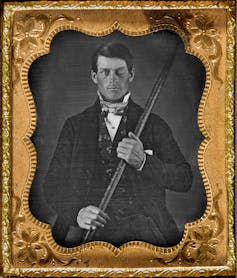

In 1848, 25-year-old Gage was working as a construction foreman for a railroad company. During the works, explosives were required to blast away rock. This intricate procedure involved explosive powder and a tamping iron rod. In a moment of distraction, Gage detonated the powder and the charge went off, sending the rod through his left cheek. It pierced his skull, and travelled through the front of his brain, exiting the top of his head at high speed. Modern day methods have since revealed that the likely site of damage was to parts of his prefrontal cortex.

Gage was thrown to the floor, stunned, but conscious. His body eventually recovered well, but Gage’s behavioural changes were extraordinary. Previously a well-mannered, respectable, smart business man, Gage reportedly became irresponsible, rude and aggressive. He was careless and unable to make good decisions. Women were advised not to stay long in his company, and his friends barely recognised him.